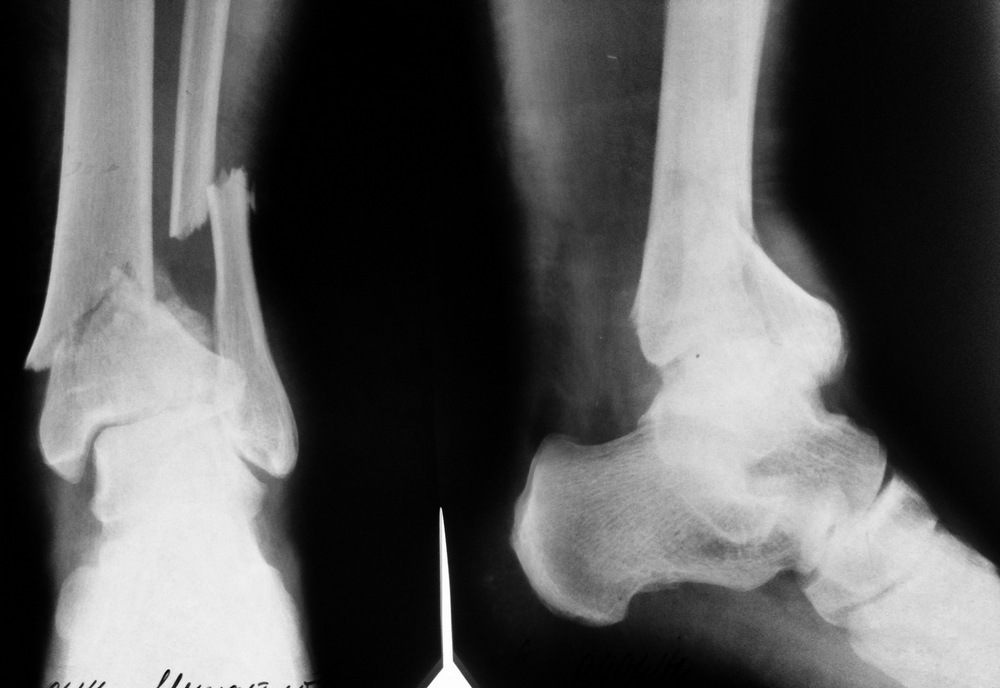

Пациент - мужчина, оперирован по поводу оскольчатого перелома пилона 43-С1 в конце января этого года.

1. ORIF малоберцовой кости 1/3 трубчатой LCP пластиной

2. ORIF пилона антеролатеральной LCP пластиной

Верхний снимок - контроль после операции